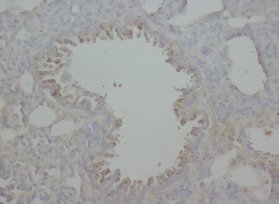

Immunohistochemical analysis of paraffin-embedded human lung tissue labeling RAGE with ab216329 at 1/4000 dilution, followed by Goat Anti-Rabbit IgG H&L (HRP) Ready to use. Membranous staining on epithelial cells of human lung (PMID : 19592063; PMID : 26472810) is observed. Counter stained with Hematoxylin.

Secondary antibody only control : Used PBS instead of primary antibody, secondary antibody is Goat Anti-Rabbit IgG H&L (HRP) Ready to use.

This data was developed using the same antibody clone in a different buffer formulation containing PBS, BSA, glycerol, and sodium azide (ab216329).

Perform heat mediated antigen retrieval with Tris/EDTA buffer pH 9.0 before commencing with IHC staining protocol.